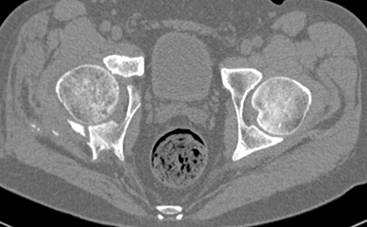

высылаю дополнительно сканы.

Судя по представленным реконструкциям (не очень хорошего качества - много наводок)

мы имеем дело с полупоперечным переломом у которого отломался задний край или его отломали, превратив перелом в полный двухколонный.

По отдельным срезам и тем более по реконструкции трудно судить о сращении крыла и задней колонны с осевым скелетом.

Пациент передвигается с помощью костылей с дозированной нагрузкой на правую ногу. При движении правой нижней конечностью ощущает щелчки. Болей в правом тазобедренном суставе в настоящее время нет. Вся правая нижняя конечность умеренно ротирована наружу.

Хорошо бы на рентгенограммы взглянуть и побольше срезов по своду. С каким отломком головка контактирует и как ее состояние.

Из того минимума, что представлено, мне кажется, мы имеем дело с двухколонным переломом вертлужной впадины. Обычно медиальный (центральный) "вывих" головки встречаются в сложных двухколонных переломах со смещением.

Дополнительные сканы